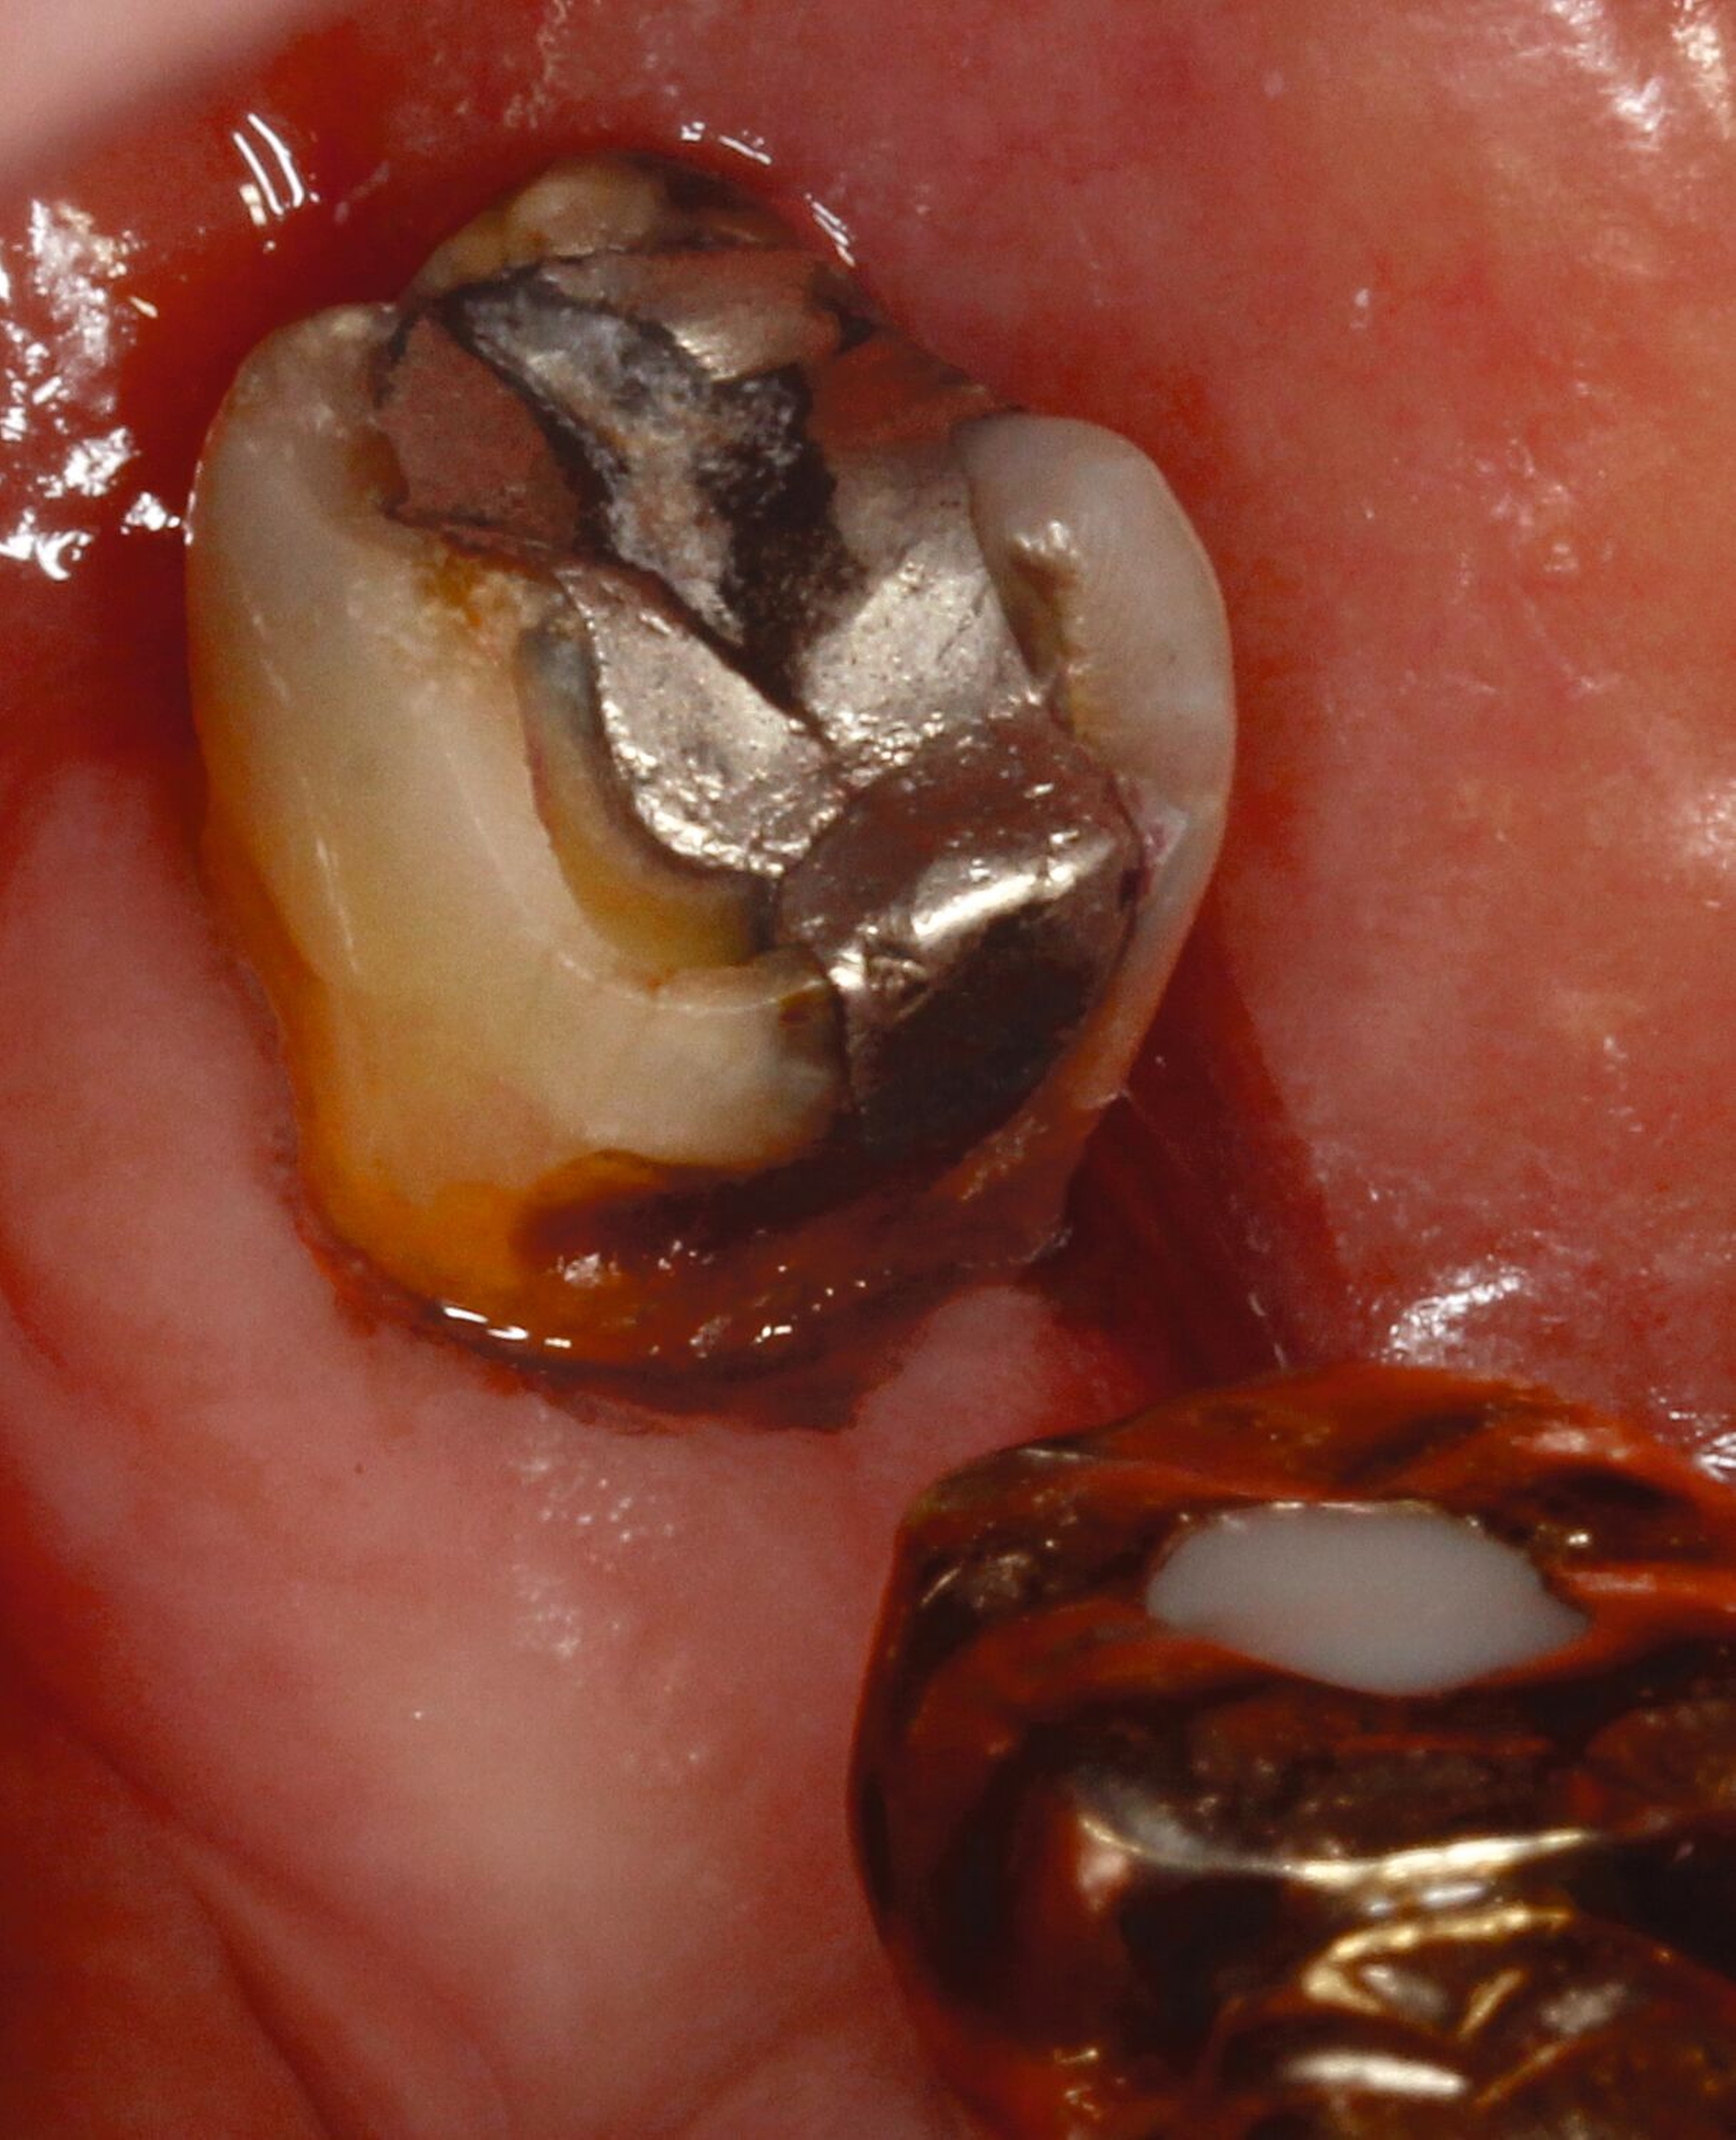

Silberdiamminfluorid ist eine wasserlösliche Verbindung, die aus Silberionen (Ag+), Ammoniak (NH₃) und Fluoridionen (F-) besteht. Ammoniak dient in dieser Verbindung als Stabilisator, indem es die Lösung alkalisch hält. Bei einer Konzentration von 38 Prozent entspricht das einer Konzentration von 44.800 ppm Fluorid und 255.000 ppm Silberionen. In seiner physikalischen Erscheinung ist SDF eine klare bis leicht gelbliche Flüssigkeit mit einem charakteristischen metallischen und leicht ammoniakartigen Geruch. Aufgrund der hohen Alkalität kann es bei Schleimhautkontakt zu leichten Reizungen kommen (Abbildung 2).

Eine bekannte Nebenwirkung bei Anwendung auf kariösen Läsionen ist die Schwarzfärbung des behandelten Bereichs (Abbildungen 3, 4). Verfärbungen können aber auch bei Applikation auf kariesfreien Wurzeloberflächen entstehen, diese sind jedoch mit einer professionellen Zahnreinigung gut zu entfernen (Abbildung 2).

Tatsächlich zeigt die klinische Erfahrung, dass es möglich ist, bei mehrmaliger Applikation innerhalb eines Vierteljahrs auch sehr aktive Läsionen mit taktil weicher Oberfläche trotz eingeschränkter Mundhygiene gut zu erhärten (Abbildung 4). Für die koronale Karies bei Kindern konnte die bessere Wirkung nach wiederholter Anwendung allerdings nicht bestätigt werden. [Smutkeeree et al., 2025].